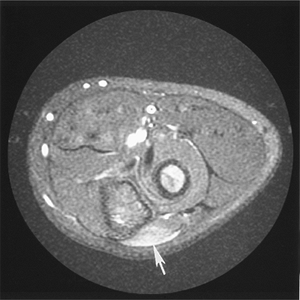

![]() |

FIGURE 8-28 Ganglion cyst. Axial T1- (A) and T2- (B) weighted images showing a benign cyst (arrow) with uniform increased intensity on T2-weighted and low signal intensity on T1-weighted sequences.